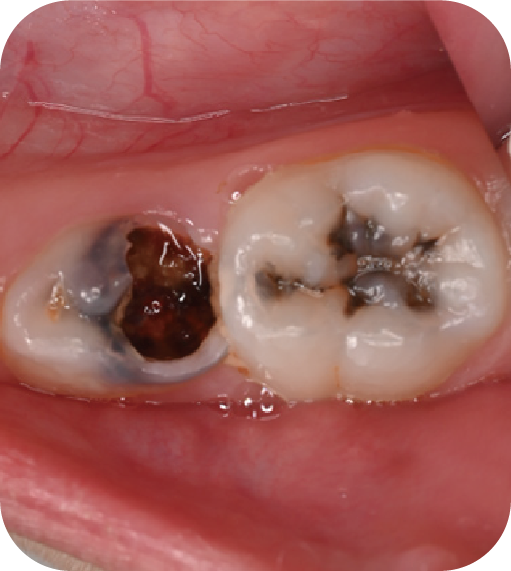

后磨牙,也就是大牙咬合面上凹凸不平的裂隙,這就是“窩溝”。窩溝有很多形狀,有的是狹長的裂隙形狀,還有的在牙齒深處又會分成幾條小溝。這些地方用牙刷很難深入清潔,于是就成了衛(wèi)生死角,細菌特別喜歡在里面生存,不斷產酸腐蝕牙齒,蛀牙就這樣產生了。如果我們用窩溝封閉把這些衛(wèi)生死角封起來,那既可以杜絕食物和細菌進入窩溝內,也可以讓窩溝處的清潔變得更簡單,這就是做窩溝封閉的目的。同時它也是世界衛(wèi)生組織、國家衛(wèi)健委都推薦的防齲方法。